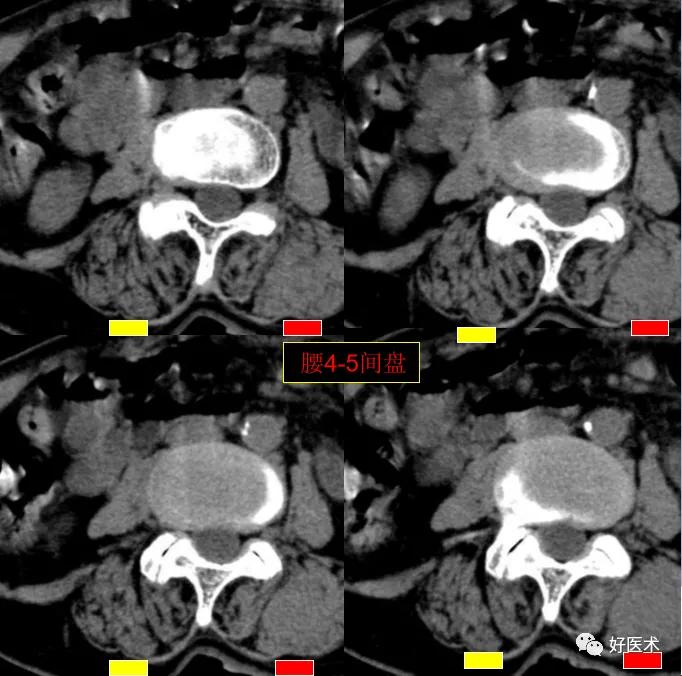

CT图像,腰椎常规采用序列扫描,腰椎体2层,腰间盘4层,层厚2.5mm,一般扫描范围包括腰2--骶1椎体及所属间盘。

腰4-5间盘膨隆, 双侧椎小关节积气

腰5骶1间盘膨隆,双侧椎小关节积气